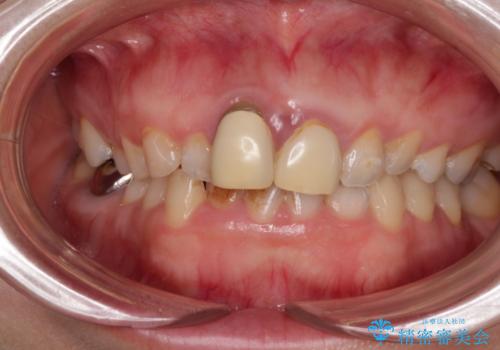

- 前歯のデコボコと、着色が著しい保険診療の前歯クラウンを気にして来院された患者様です。

左上の犬歯が埋伏しており、CT画像より萌出は困難と判断されたため、残存している歯にて歯列と咬合を整えることとしました。

前歯のクラウンは変色が顕著なため、矯正治療後にオールセラミッククラウンによる補綴治療を行うこととしました。